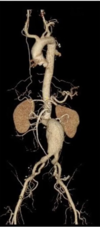

What are the 3 key benefits of using CT scanners?

- quick and widely available

- cross sectional images instead of 2D

- high contrast resolution (good for soft tissue)